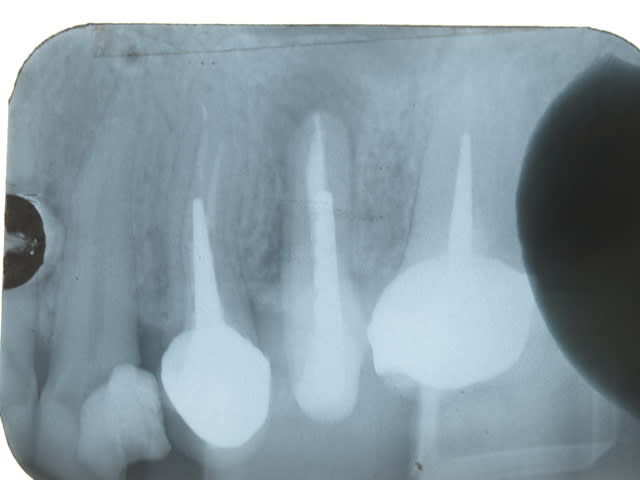

la radio est a environ 3 semaines apres la reimplantation .

tu as vu la bestiole ? elle etait le long de la racine et pas qu' au bout. t imagine la resection qu il aurait fallu faire ?

en tout cas sur la radio du depart ça paraissait pas aussi important.

et tu t'inquiete pour le ligament ? moi non .